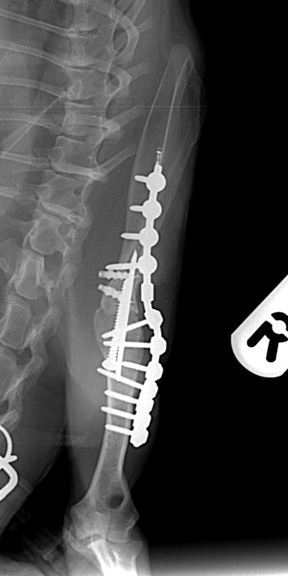

Radiographs taken 8 weeks after surgery showed good progression of arthrodesis and no evidence of any implant associated problems.

Figures 3 & 4. Mediolateral and caudocranial radiographs of the arthrodesed shoulder 8 weeks after surgery, showing good progression of arthrodesis and good alignment of the shoulder and elbow joints with the shoulder at a standing angle.